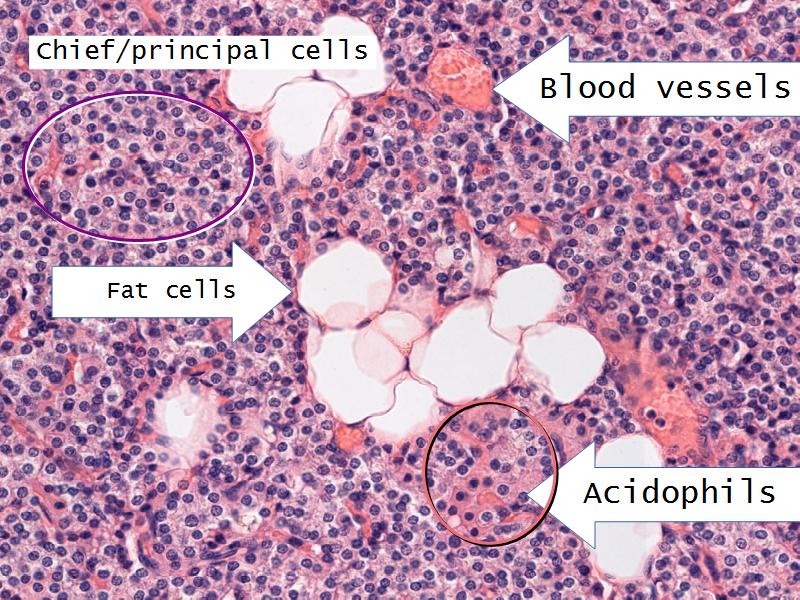

Chief cells = majority

Oxyphil (acidophil) = single/groups